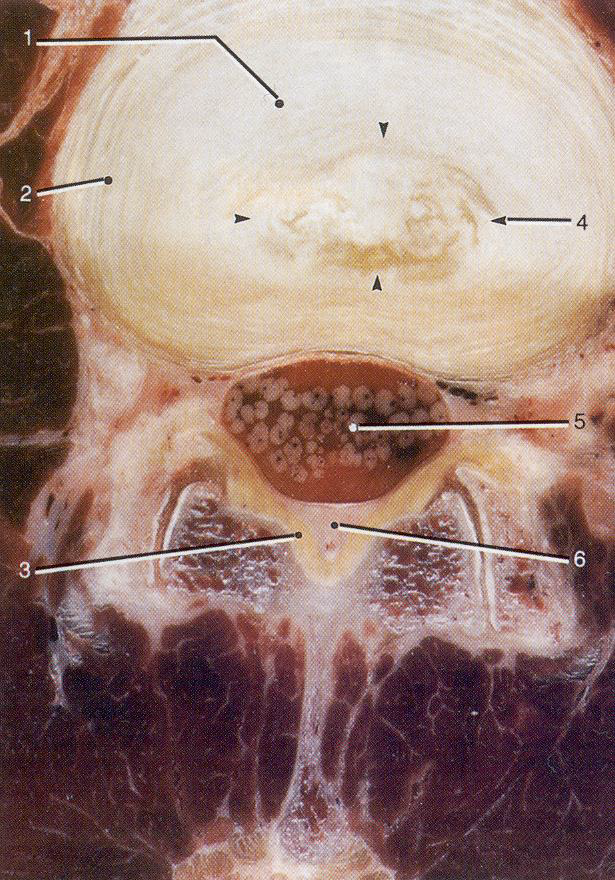

Анатомический срез

МРТ (аксиальная томограмма)